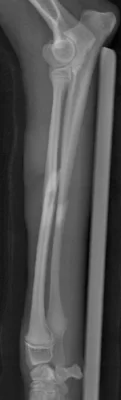

右前肢

右前肢はLag Screw固定の併用が可能だったので1期癒合

右前肢は骨片間圧迫を加えているため、骨折端同士が直接癒合します。

そのため仮骨形成が少なく、早期に癒合します。

術後19日 右前肢は治療終了です。